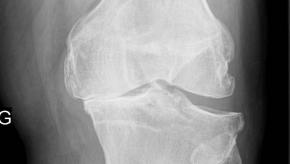

What’s new in knee osteoarthritis that matters?

Are intra-articular steroid injections effective in symptomatic knee OA? Do they accelerate cartilage loss? Does weight less actually help? Do we have DMARDs for knee OA? Insights from 2020 ACR Convergence.